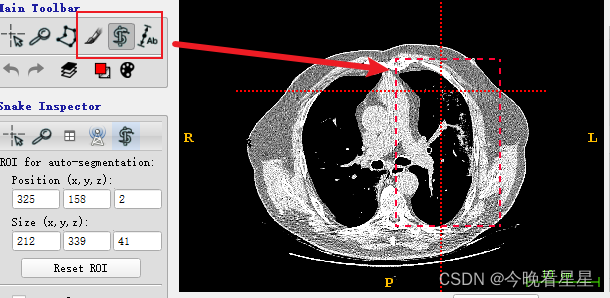

4 半自动分割的步骤

**半自动分割的基本过程: **

-

使用矩形框进行框选,并在多个视图中确定区域

-

在左侧进行3D分割

- 看第二个视图, 蓝色为丢弃区域,白色为选择的区域,进行CT阈值的调节,来选择想要的部分。参数调整完毕后,选择next进行下一步操作